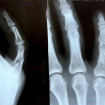

• Лечение кисти, в том числе после травм,

резаных ран, повреждений сухожилий,

а также удаление доброкачественных новообразований

в суставах (в том числе болезненных).